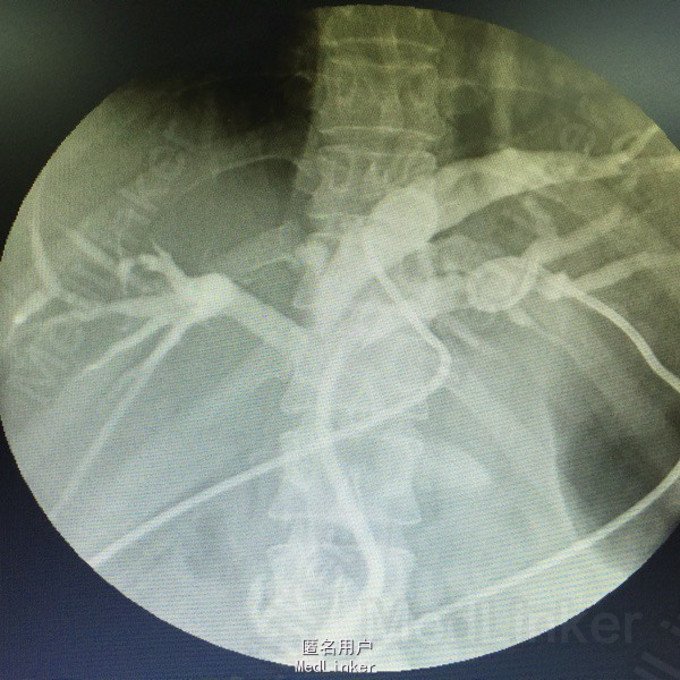

是左肝外叶胆管结石还是肝内胆管汇合部结石?

患者中年女性,做过胆切,肝总管切开取石,T管支撑引流术的,术中发现左肝内胆管畸形梗阻,胆囊位置变异,胆道术后开始腹痛,发高烧,考虑结石复发。 一下CT和放射片来看,结石到底在哪?